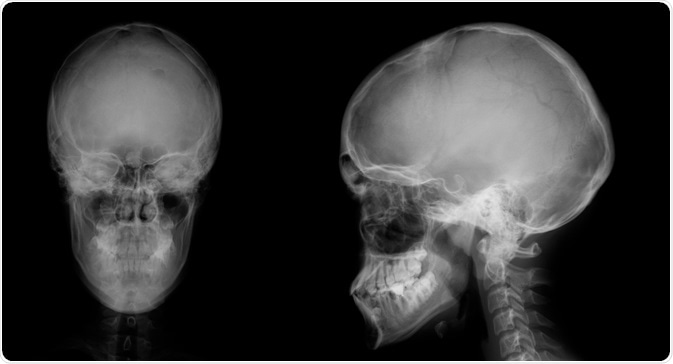

Gardner syndrome is often first identified in a dental clinic, as it is associated with odontomas and impacted teeth at multiple sites that can be both permanent and supernumerary. In fact, about 30% of patients with Gardner’s syndrome have one or more dental anomaly.

Image Credit: Rames Khusakul / Shutterstock.com

Maxillofacial involvement is very common in these patients and can involve skin cysts, pigmentation, and various radiographic anomalies. Odontomas also arise in the paranasal sinuses and mandible, and are rarely painful, generally occurring after puberty.

Multiple osteomas also occur in Gardner's. The most common site for these types of tumors is the mandible, specifically at the angle of the jaw and the inferior surface of this bone. Additional osteomas may be present in the skull, paranasal sinuses, and long bones.

Image Credit: vanzittoo / Shutterstock.com

Osteomas occur early in the course of the disease, typically before colonic polyps become symptomatic or are picked up by radiography. In fact, it is not uncommon for osteomas to develop in Gardner syndrome patients before the condition is even diagnosed. For this reason, the presence of osteomas should arouse curiosity as to the presence of Gardner’s syndrome, as they offer a window of opportunity for early diagnosis and possible prevention of colonic cancer. A number of researchers, therefore, suggest that radiography of the mandible may help to screen for carriers of this condition.

Both osteomas and odontomas may cause the face to become asymmetric. Both sharply-defined radio-opaque lesions as well as fuzzy radio-opaque lesions can be visualized in patients with Gardner's syndrome.